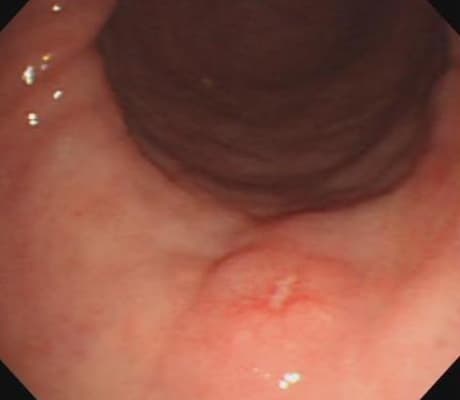

先端の太さが5.4㎜で、鉛筆と同程度の非常に細い胃カメラで検査を行っておりますので、苦痛なく検査が行えます。通常の観察に加え、NBIという技術を用いた特殊光観察を行うことができます。NBIとはNarrow Band Imaging (狭帯域光観察)の略で、特殊な光を使って粘膜表面を色調を変えて観察することにより、がんの早期発見や炎症などの他の原因との鑑別診断に役立ちます。